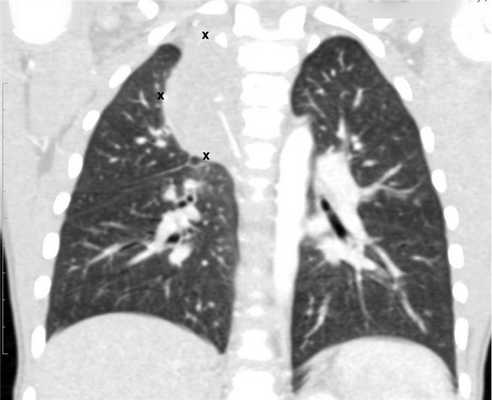

Компьютерная томография органов грудной клетки, брюшной полости, малого таза используются для оценки распространения опухолевого процесса (рис.5).

Рисунок 6. — КТ органов грудной клетки - семинома средостения.